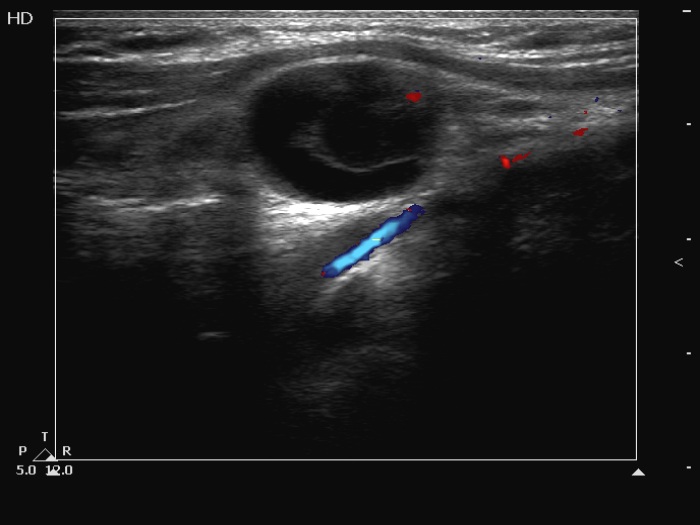

Before surgery (ultrasonographic picture 12)

Left submandibular area, transverse scan, color Doppler mode. The solitary vascular spot has great relevance, it proves that this is not a clot but a solid area.